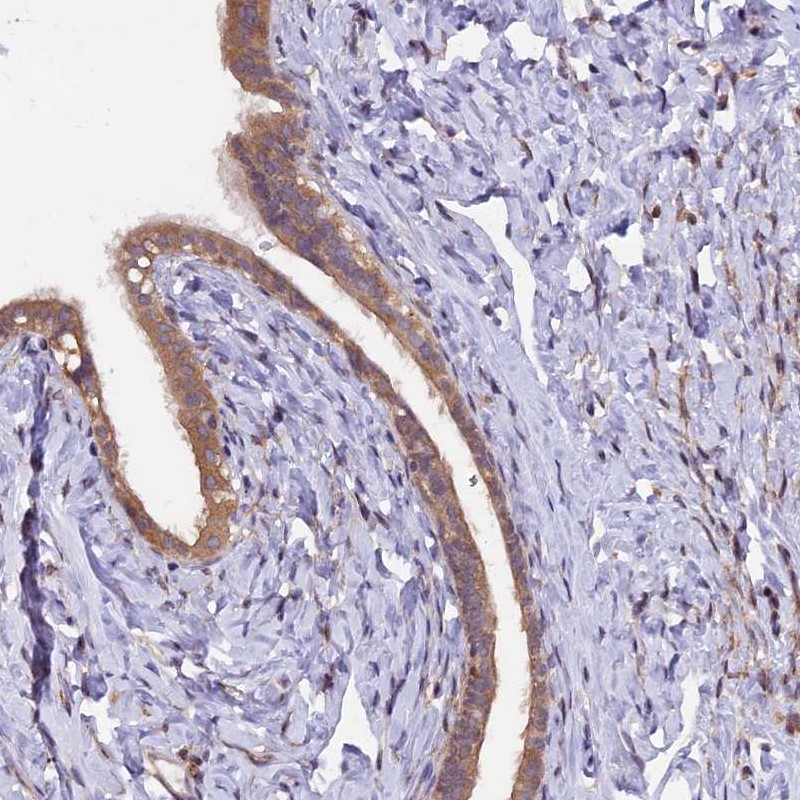

Immunohistochemical staining of human fallopian tube shows cytoplasmic positivity in glandular cells.